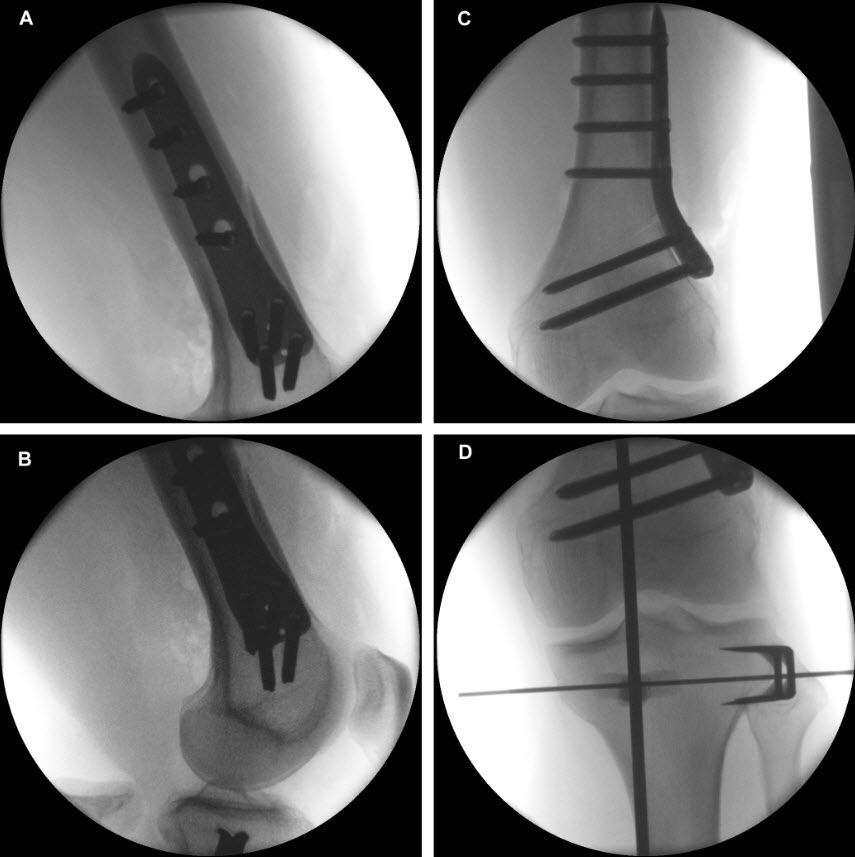

The TomoFix Anatomical Medial High Tibial Plate is contoured to provide an anatomical fit. When compared with the TomoFix Standard and small plates, the new design is intended to reduce both implant prominence

and postoperative implant irritation. Fig 1 shows x-rays from one patient.